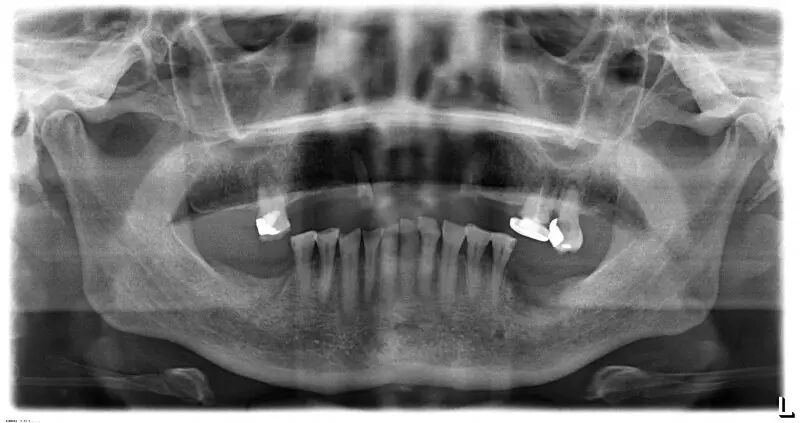

>>>口腔数字化CT、数字化X光检查系统、国际标准的消毒设备、进口的根管测量仪、进口根管治疗仪、进口洁牙机、进口喷砂机、完全能达到无菌操作的口腔综合治疗椅。

价值90元的全景拍片+价值180元的口腔数字化CT不要钱免费做,口腔问题一步解决